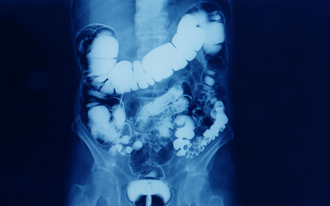

小心宿便清到腸道變色 1類瀉藥害黑腸症 醫教判斷

過度依賴瀉藥,可能造成黑腸症。醫師黃郁純指出,長期服用含有蒽醌類成分的瀉藥或保健食品,會刺激腸道黏膜,導致變黑,這些產品常會以幫助排便、清宿便、體內環保等名義販售,購買時可留意是否含有番瀉葉、大黃、蘆薈、鼠李皮等成分。